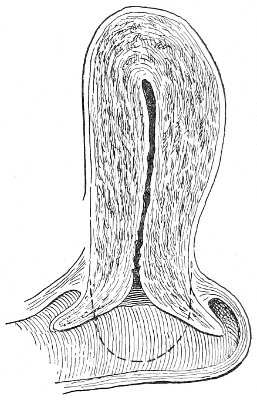

An accurate knowledge of the anatomy and mechanism of the female perineum is essential to an understanding of the nature and treatment of injuries to this structure. The anatomical structures lying between the anus behind and the symphysis pubis in front are those that most directly interest the gynecologist. Proceeding from 57 below upward, we find the following structures lying in superimposed planes: the skin, the superficial fascia, the deep layer of the superficial fascia, the transversus perinæi and the sphincter vaginæ muscles, the anterior layer of the triangular ligament, the posterior layer of the triangular ligament, the levator ani muscle (Fig. 19).

The vagina passes through these structures. They surround and support the ostium vaginæ as the fascia and muscles surround and support the opening of the rectum or the anus. The muscles and fasciæ are attached in the median line between the anus and the vagina, and therefore this part of the body, which is called the perineum, is supported or maintained in its 58 proper position by these various structures. The transversus perinæi arises from the ramus of the ischium and is inserted in the perineum. The bulbo-cavernosus, or sphincter vaginæ, arises in the perineum and is inserted in and about the clitoris. The inner fibers of the levator ani arise from the symphysis pubis and are inserted in the perineum and the lower part of the vagina (Fig. 20). When these muscles contract, their action, therefore, is to draw the perineum upward and forward. At the same time the anus is drawn upward and forward, and so also is the posterior margin of the ostium vaginæ and the lower portion of the posterior vaginal wall.

The vagina has no circular sphincter like the anus, but 59 the vaginal month is kept closed by the action of the transversus perinæi, sphincter vaginæ, and levator ani muscles, which draw the perineum forward, and thus keep the posterior vaginal wall in apposition with the anterior wall.

This sling of muscles and fascia, which surrounds and supports the opening of the vagina, may readily be felt in the nulliparous woman by introducing the finger in the vagina and pressing backward and outward toward the ischio-rectal fossa. We then feel plainly, immediately within the ostium vaginæ, a firm resisting band of tissue, apparently about half an inch broad, embracing the posterior portion of the lower vagina. This band is formed by the inner edges of the various muscles and planes of fascia that have been described.